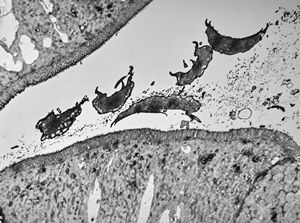

Giardia (Lamblia) intestinalis